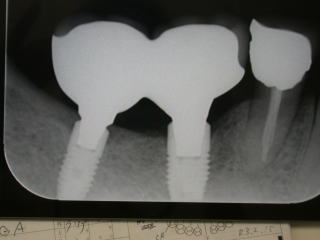

症例11、60才代男性(新潟県長岡市要町 要町歯科歯科 インプラント)

右下6番、7番にインプラントを稙立し、白い被せものを入れました。

稙立は2021年2月16日です。

上部構造物(白い歯)の装着は2021年8月11日です。